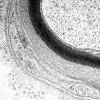

PERIPHERAL NEUROPATHY